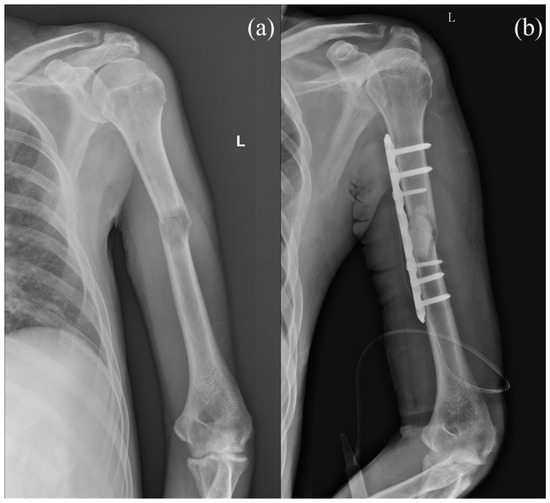

PF is commonly used in patients with solitary lesions because it provides a direct approach to the lesion, enabling the surgeon to explore the border of the tumor while preserving shoulder function with a better operating view, maintaining the integrity of the rotator cuff and lessening tumor burden (Figure 1) [5]. However, concerns regarding PF include potential postoperative radial nerve palsy, a larger incision leading to increased wound complications, and the relatively limited fixation length [5,6].

Figure 1. (a) Preoperative image of a case with diffuse liver tumor and left pathological humeral shaft fracture. (b) Plate fixation with cement augmentation was performed for the pathological humeral shaft fracture. Letter “L” in the figure are referred to as left.